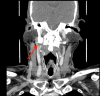

Eagle's syndrome is a rare cause of cervicofacial pain and is due to abnormalities in the stylohyoid process, stylohyoid ligament or lesser cornu of the hyoid bone. Generally, patients affected by Eagle's syndrome present with pain in the lateral or upper neck, angle of the mandible, submandibular space and throat (exacerbated by head movements and/or mastication); foreign body sensation; headache and referred otalgia. A 66-year old gentleman presented with a 36-month history of recurrent pain localising mainly to the right angle of the mandible and radiating to the submandibular triangle. No pathological changes were noted on multiple ultrasound scans. Flexible nasendoscopy revealed a right vocal cord palsy. Initially, the CT scan revealed an abnormality in the stylohyoid complex, and the patient was managed conservatively. Subsequent three-dimensional CT scan noted significant worsening of the abnormality in the stylohyoid complex. Due to progressive nature of the patient's symptoms and progression of stylohyoid complex calcification noted on imaging, the patient was listed for surgery. He underwent partial styloidectomy and vocal cord injection for cord paralysis secondary to impingement on the vagal nerve by the stylohyoid complex. The patient recovered well and denies any ongoing stylalgia. Various cases of Eagle's syndrome have been managed successfully in a conservative manner. However, the authors of this case report suggest that patients with Eagle's syndrome should be monitored closely. A delay in surgical intervention can lead to complications such as complete ossification of the stylohyoid complex and impingement on surrounding structures. This, in turn, increases intra-operative complexity.